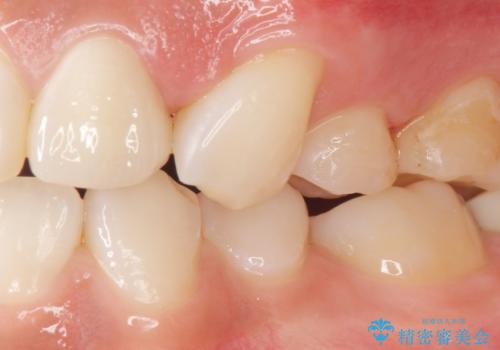

矯正せずに早く治したいという強いご希望により、セラミッククラウンによる補綴治療(上顎両側2の2本)を行いました。

天然歯のような自然な仕上がりに大変喜んで頂けました。

クラウンの種類:オールセラミッククラウン スペシャル